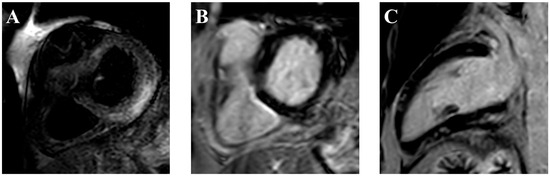

- Messroghli, D.R.; Moon, J.C.; Ferreira, V.M.; Grosse-Wortmann, L.; He, T.; Kellman, P.; Mascherbauer, J.; Nezafat, R.; Salerno, M.; Schelbert, E.B.; et al. Clinical recommendations for cardiovascular magnetic resonance mapping of T1, T2, T2 * and extracellular volume: A consensus statement by the Society for Cardiovascular Magnetic Resonance (SCMR) endorsed by the European Association for Cardiovascular Imaging (EACVI). J. Cardiovasc. Magn. Reson. 2017, 19, 75. [Google Scholar] [CrossRef] [PubMed]

- Ferreira, V.M.; Schulz-Menger, J.; Holmvang, G.; Kramer, C.M.; Carbone, I.; Sechtem, U.; Kindermann, I.; Gutberlet, M.; Cooper, L.T.; Liu, P.; et al. Cardiovascular Magnetic Resonance in Nonischemic Myocardial Inflammation. J. Am. Coll. Cardiol. 2018, 72, 3158–3176. [Google Scholar] [CrossRef] [PubMed]

- Cadour, F.; Cautela, J.; Rapacchi, S.; Varoquaux, A.; Habert, P.; Arnaud, F.; Jacquier, A.; Meilhac, A.; Paganelli, F.; Lalevée, N.; et al. Cardiac MRI Features and Prognostic Value in Immune Checkpoint Inhibitor–induced Myocarditis. Radiology 2022, 303, 512–521. [Google Scholar] [CrossRef] [PubMed]

- Higgins, A.Y.; Arbune, A.; Soufer, A.; Ragheb, E.; Kwan, J.M.; Lamy, J.; Henry, M.; Cuomo, J.R.; Charifa, A.; Gallegos, C.; et al. Left ventricular myocardial strain and tissue characterization by cardiac magnetic resonance imaging in immune checkpoint inhibitor associated cardiotoxicity. PLoS ONE 2021, 16, e0246764. [Google Scholar] [CrossRef] [PubMed]

- Thavendiranathan, P.; Zhang, L.; Zafar, A.; Drobni, Z.D.; Mahmood, S.S.; Cabral, M.; Awadalla, M.; Nohria, A.; Zlotoff, D.A.; Thuny, F.; et al. Myocardial T1 and T2 Mapping by Magnetic Resonance in Patients with Immune Checkpoint Inhibitor-Associated Myocarditis. J. Am. Coll. Cardiol. 2021, 77, 1503–1516. [Google Scholar] [CrossRef] [PubMed]